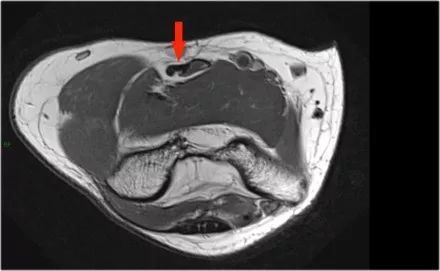

下面是一名18岁的棒球投手,内侧肘部疼痛。看到局部撕裂产生'T标志'。

下面的图像,请注意,前束是完整的,并牢固地附着在崇高的结节上(黄色箭头)。在接下来的两张图像上,有一些软组织水肿,后面有更多异常信号(红色箭头)。所以我们怀疑后束的病理学。现在你记得轴向图像可能会有所帮助。

在下面轴向图像上,我们很好地看到前束是o.k. (红色箭头)。它旁边只有一些水肿。

然而,后束不是o.k,有一部分撕裂。这种情况我们偶尔会在投掷运动员中看到,前束完整,肘部不稳定。他们以某种方式撕裂了他们的后束,导致疼痛。他们不需要手术,但它仍然可能让他们在游戏中停留很长一段时间。